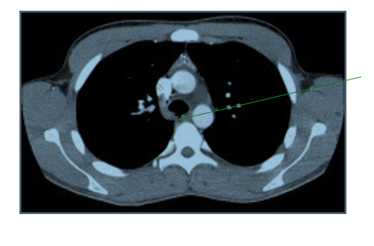

While still in the emergency department, he continued to have hemoptysis and developed palpable surgical emphysema at the root of the neck which raised suspicion of an ongoing air-leak from a TBI. A CT scan of the thorax was done and it showed a posterior tracheal tear 1.5cm above the carina as shown in Figure 2 and bilateral lung contusions, shown in Figure 3. His dyspnea and surgical emphysema continued to worsen, so he was intubated and immediately transferred to the nearest cardiothoracic centre.

Figure 2 CT Thorax transverse view showing posterior defect in the trachea.